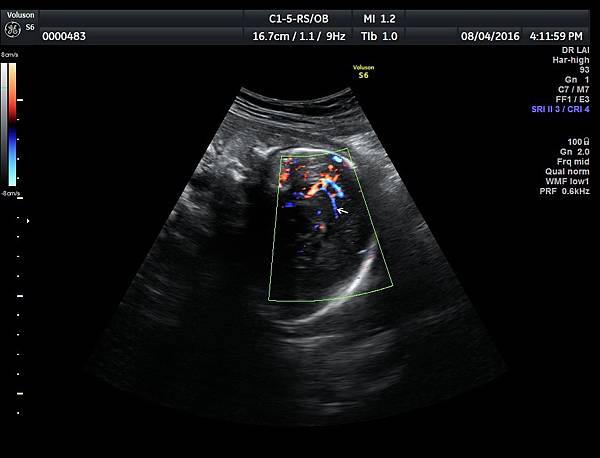

2016年8月4日在執行胎兒高層次超音波檢查時,我發現胎兒腦部的CSP(cavum septum pellucidum)很不清楚(附圖1~4),遇到這種情況,需要仔細評估胎兒腦部的駢胝體,因為CSP的天花板是駢胝體,CSP不明顯時,要合理的懷疑駢胝體沒有發育,或駢胝體下方有長東西(例如lipoma),駢胝體是連接左右大腦的神經纖維所組成。

1. 矢狀切面(sagittal plane):駢胝體呈現類似三明治的中間黑色部分,上面一層薄薄白色的區域是callosum sulcus,打上flow可以看到pericallosum artery在駢胝體上面的周圍,pericallosum artery來源是前腦動脈,參考附圖 6~10,三明治下面白白的部分是和CSP做比較得到的,如果這一層長lipoma(附圖 5),CSP很可能看不到。